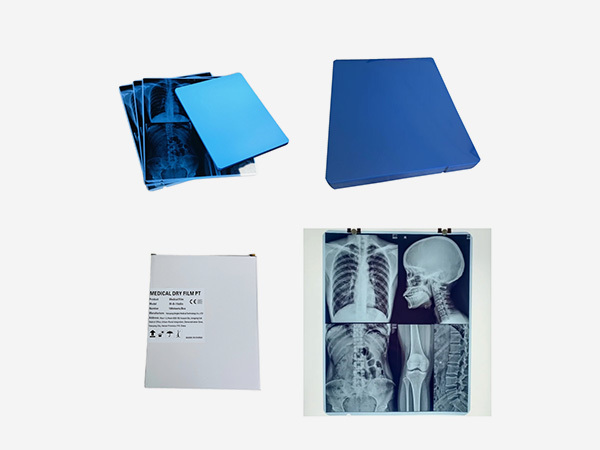

Independently develops and produces thermal film, medical laser film, and medical printing Film and other products.

As an indispensable and important tool in the medical diagnosis process, medical film plays a crucial role in disease detection, diagnosis, and treatment tracking.

Common types include X-ray films, CT films, and MRI films. X-ray films are used for general radiography, while CT and MRI films display detailed cross-sectional images of the body, aiding in accurate diagnosis and treatment planning.

The shelf life of medical films typically ranges from 1 to 3 years, depending on the type. Films should be stored in a cool, dry place away from direct sunlight, radiation, and magnetic fields. Maintain a temperature between 10 - 20°C and humidity around 40 - 60% to ensure optimal quality.